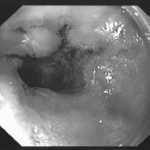

діагностика

Виявляється патологія після дослідження біоптату слизової, яка проводиться в процесі ФГДС. У препараті виявляють характерні змінені клітини, які продукують сульфамуцін. Ця речовина здатна абсорбувати на собі канцерогени, які провокують розвиток онкології.

Також клітини змінюють склад своїх антигенів: з'являється раково-ембріональний антиген (свідоцтво зниження диференціювання клітин), підвищений рівень якого виявляють у крові. В результаті проведених досліджень виставляється діагноз, в формулюванні якого враховуються розміри і місце знаходження метаплазії, наприклад, вогнищева кишкова метаплазія слизової антрального відділу шлунка.